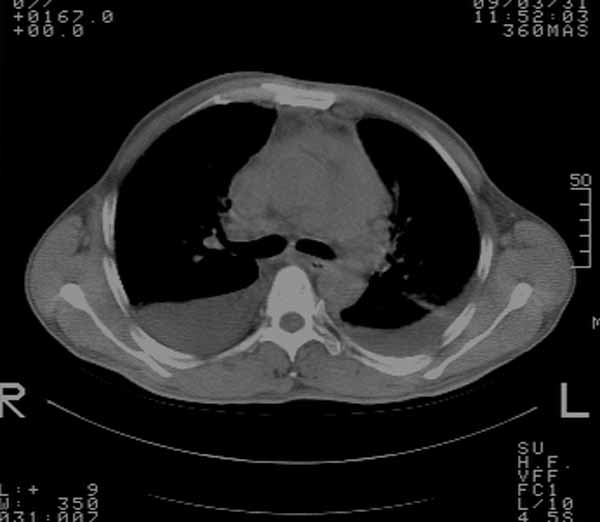

以下是引用余辉在2009-3-31 18:43:00的发言:[br]肺水肿,双侧心腔积液,心包积液,心影增大,疑似心衰

以下是引用wangyong1977在2009-3-31 20:46:00的发言:[br]肺水肿,双侧胸腔积液,心包积液,心影增大,疑似心衰 [br]

以下是引用宇宙ct在2009-3-31 18:57:00的发言:[br]肺水肿,双侧心腔积液,心包积液,心影增大,疑似心衰 [br] [br]